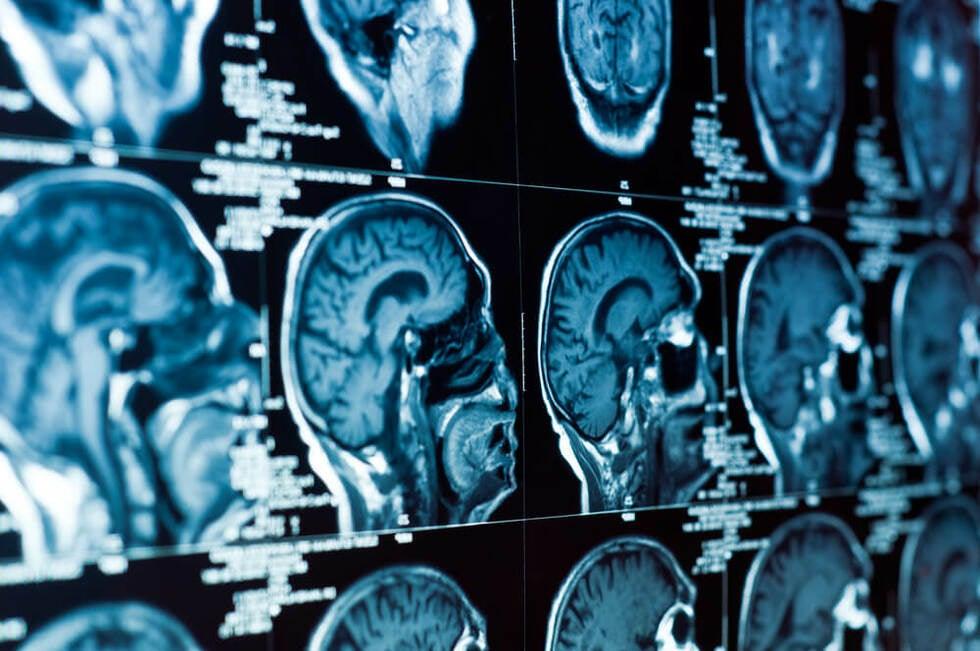

If you experience any of these signs and symptoms, you should go to a hospital or emergency department right away. It is best to seek medical attention immediately after a car accident brain injury. Your doctor may suggest diagnostic tests or brain scans to determine the extent or scope of your brain injury.